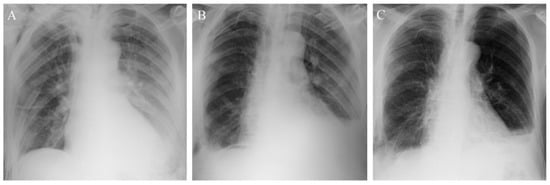

3.1. Patient 1

3.2. Patient 2

3.3. Patient 3